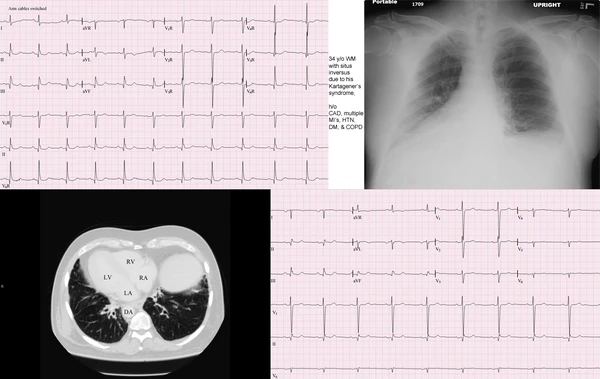

Синдром Картагенера

Синдро́м Картагенера (англ. Kartagener syndrome) — редкое наследственное заболевание человека, относящееся к группе цилиопатий. Данный синдром известен так же как англ. Ciliary dyskinesia, primary (CILD).

Синдром Картагенера характеризуется такими клиническими признаками, как транспозиция внутренних органов (situs viscerum inversus), аномалии мукоцилиарного клиренса, хронический бронхит, хронический риносинусит, хронический отит, мужское бесплодие.